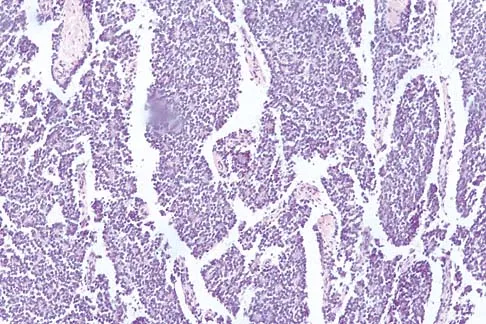

A 16-year-old boy has had thigh pain for the past several months. He denies any history of trauma. Examination reveals a large, deeply fixed, soft-tissue mass in the thigh. Laboratory results show an elevated erythrocyte sedimentation rate (ESR) and leukocytosis. A plain radiograph and MRI scan are shown in Figures 1a and 1b. Biopsy specimens are shown in Figures 1c and 1d. What is the most likely diagnosis?